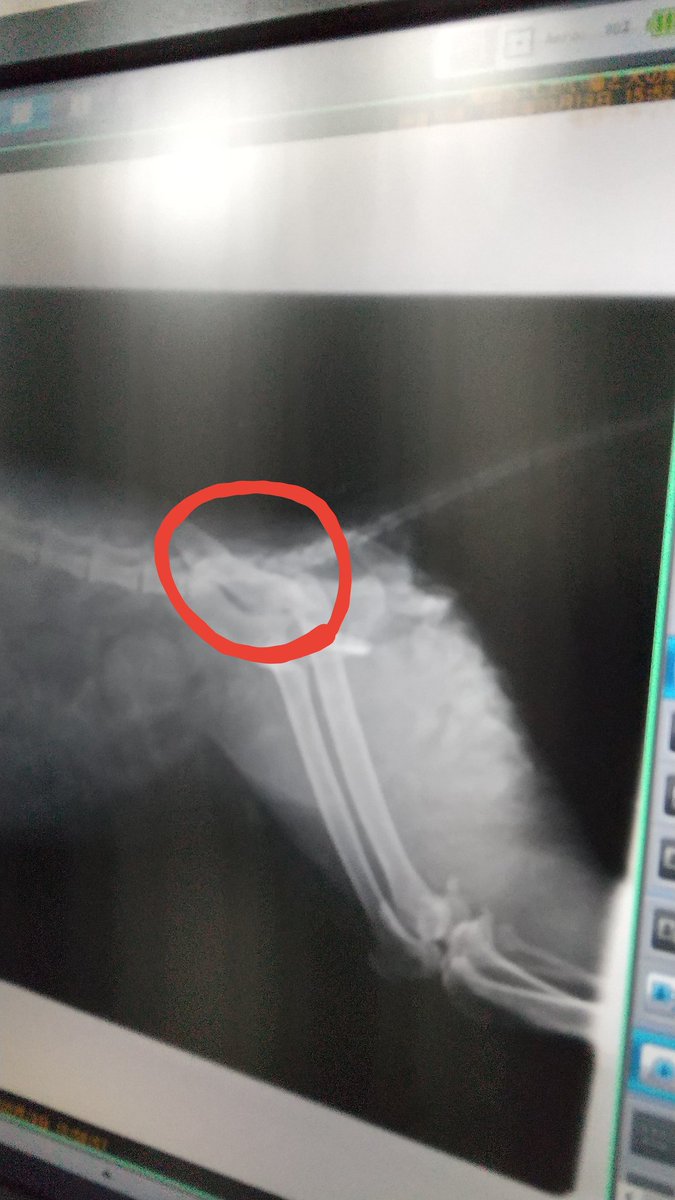

私が駆けつけた時はシェルター近くの方が溝から上げてくれてたけど便も出て下半身が麻痺してました。お腹から下を轢かれてしまったようです。助かっても下半身麻痺、圧迫排尿や排便をしなければならない。今は事故直後の影響か肺や心臓にも異常あり今日から3日間が山だそうです。1%の望みがあるなら…